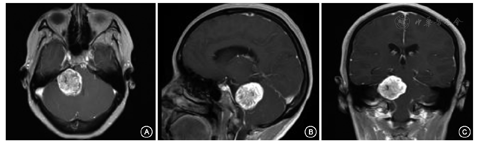

术中及术后面神经诱发电位及其传导均无明显变化(图2),术后肿瘤完全切除且面听神经走行清晰可见;术中诱发肌电图可见刺激面神经后产生动作电位(图3,图4,图5)。术后3 d两组患者的听力下降后组症状差异无统计学意义(P>0.05);但监测组术后麻木症状发生率显著低于非监测组,面神经功能分级表现也较非监测组有显著提高,差异均有统计学意义(P<0.001);同时发现监测组的面神经功能分级仍然显著优于非监测组(χ2=8.225,P=0.004);而术后1个月监测组其预后GOS评分明显高于非监测组,差异均有统计学意义(P<0.001)(表3)。

所有患者肿瘤均安全切除(图5),监测组出现并发症总人数5例(颅内感染4例:其中1例合并脑脊液漏,吞咽困难1例),非监测组出现并发症总人数10例(单纯颅内感染4例,单纯脑脊液漏2例,颅内感染合并脑脊液漏2例,手术局部渗血2例),经比较,两组术后出现并发症总例数差异无统计学意义(χ2=0.814,P=0.367),脑脊液漏发生率比较,其Fisher精确概率法P=0.691,颅内感染发生率比较,其Fisher精确概率法P=1.000。均未见显著差异。可见手术技术效果无明显差别。

近年来随着神经电生理监测技术及设备大大提高,面神经监测被广泛应用于临床,以保障手术的安全性及有效性[14]。既往关于面神经监测效果的报道中部分研究中无对照研究,多数为个案报道,评价意义不大。张磊等[15]报道244例乙状窦后入路听神经瘤切除患者,并进行回顾性研究。其报道中监测组与非监测组术前关于瘤体直径,手术方式等均有显著差异,通过Logistic回归分析认为面神经监测对神经保护有显著意义。但笔者认为其研究时间跨度较大,术者技术水平的差异所造成的差异仍有待考究。本次研究对入组患者随机分组,且手术均由同一个团队于2年内完成,术前统计其一般情况及相关症状均无显著差异,充分确保前提的统一性,使后期结果更有说服力。本次研究中监测组术后面神经功能Ⅰ~Ⅱ级者占74.3%,而非监测组则仅为42.2%,此外,监测组的面神经功能分级仍然显著优于非监测组(χ2=8.225,P=0.004),同时我们也对Ⅰ~Ⅳ级的人数进行了非参数检验分析,其χ2=-4.244,P<0.001,同样具有显著差异。对于术后面部麻木症状,经统计学比较发现监测组术后面部麻木发生率较非监测组显著降低,但其听力状况却未见明显改善。我们认为听神经鞘瘤附着于听神经鞘生长,对听神经的压迫或其他损伤较面神经严重,因此其听力改善应属于一个长期过程,但术后面瘫级面部麻木却是其监测效果的一个短期直观反应。且本次研究对患者进行了术后随访,随访结果表明监测组其远期预后明显优于非监测组预后GOS评分,同样说明面神经监测在手术过程中对神经功能的保护作用。